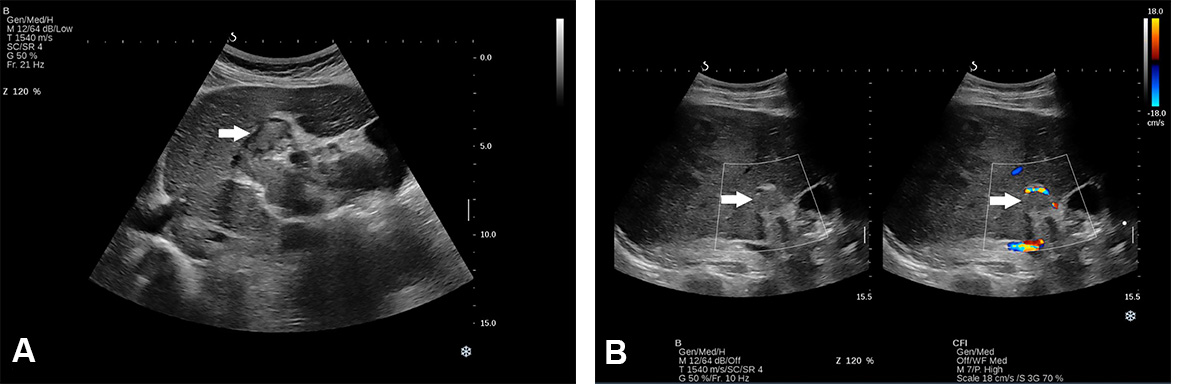

A “halo sign” is found in HCC with a fibrous capsule, but it can be found in benign tumours as well[15,17]. Thus, based only on the information provided by B mode, a differential diagnosis is not possible, and additional information concerning intratumoral vascularity is necessary [Figures 2 and 3].

Figure 2. Conventional US revealed a hypoechoic lesion in segment VII in a 71-year-old man with non-alcoholic liver cirrhosis. Ultrasound attenuation can be observed in deep segments. The lesion was a hepatocellular carcinoma.

Figure 3. Conventional US revealed an isoechoic lesion with a hypoechoic halo in a 23-year-old woman diagnosed with non-alcoholic liver steatosis (arrow). CEUS examination followed, and, based on the contrast behaviour, the final diagnosis was focal nodular hyperplasia.